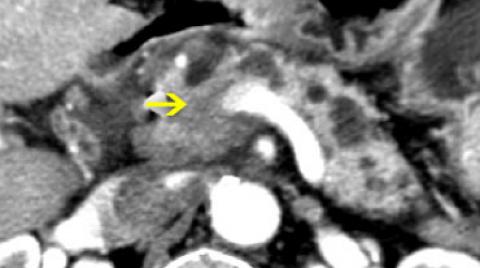

That's why I knew I was lucky, relatively speaking, to be diagnosed with a less aggressive neuroendocrine tumor that could be cured with surgery

In 2017, I underwent the Whipple operation to remove my dominant cancer from the head of my pancreas